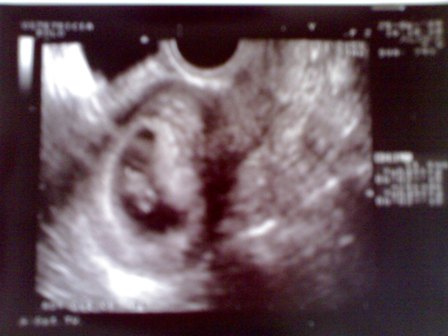

Viszont van egy kep amit mindenkeppen szeretnek veletek megosztani:

Kép

Velünk is megtörtent a csoda, me'g ma is nehezen hiszem de mivel mar uh-n is lattam biztos a dolog... a kilencedik het elejen jarok es nagyon remelem, hogy minden jol alakul ezutan is.